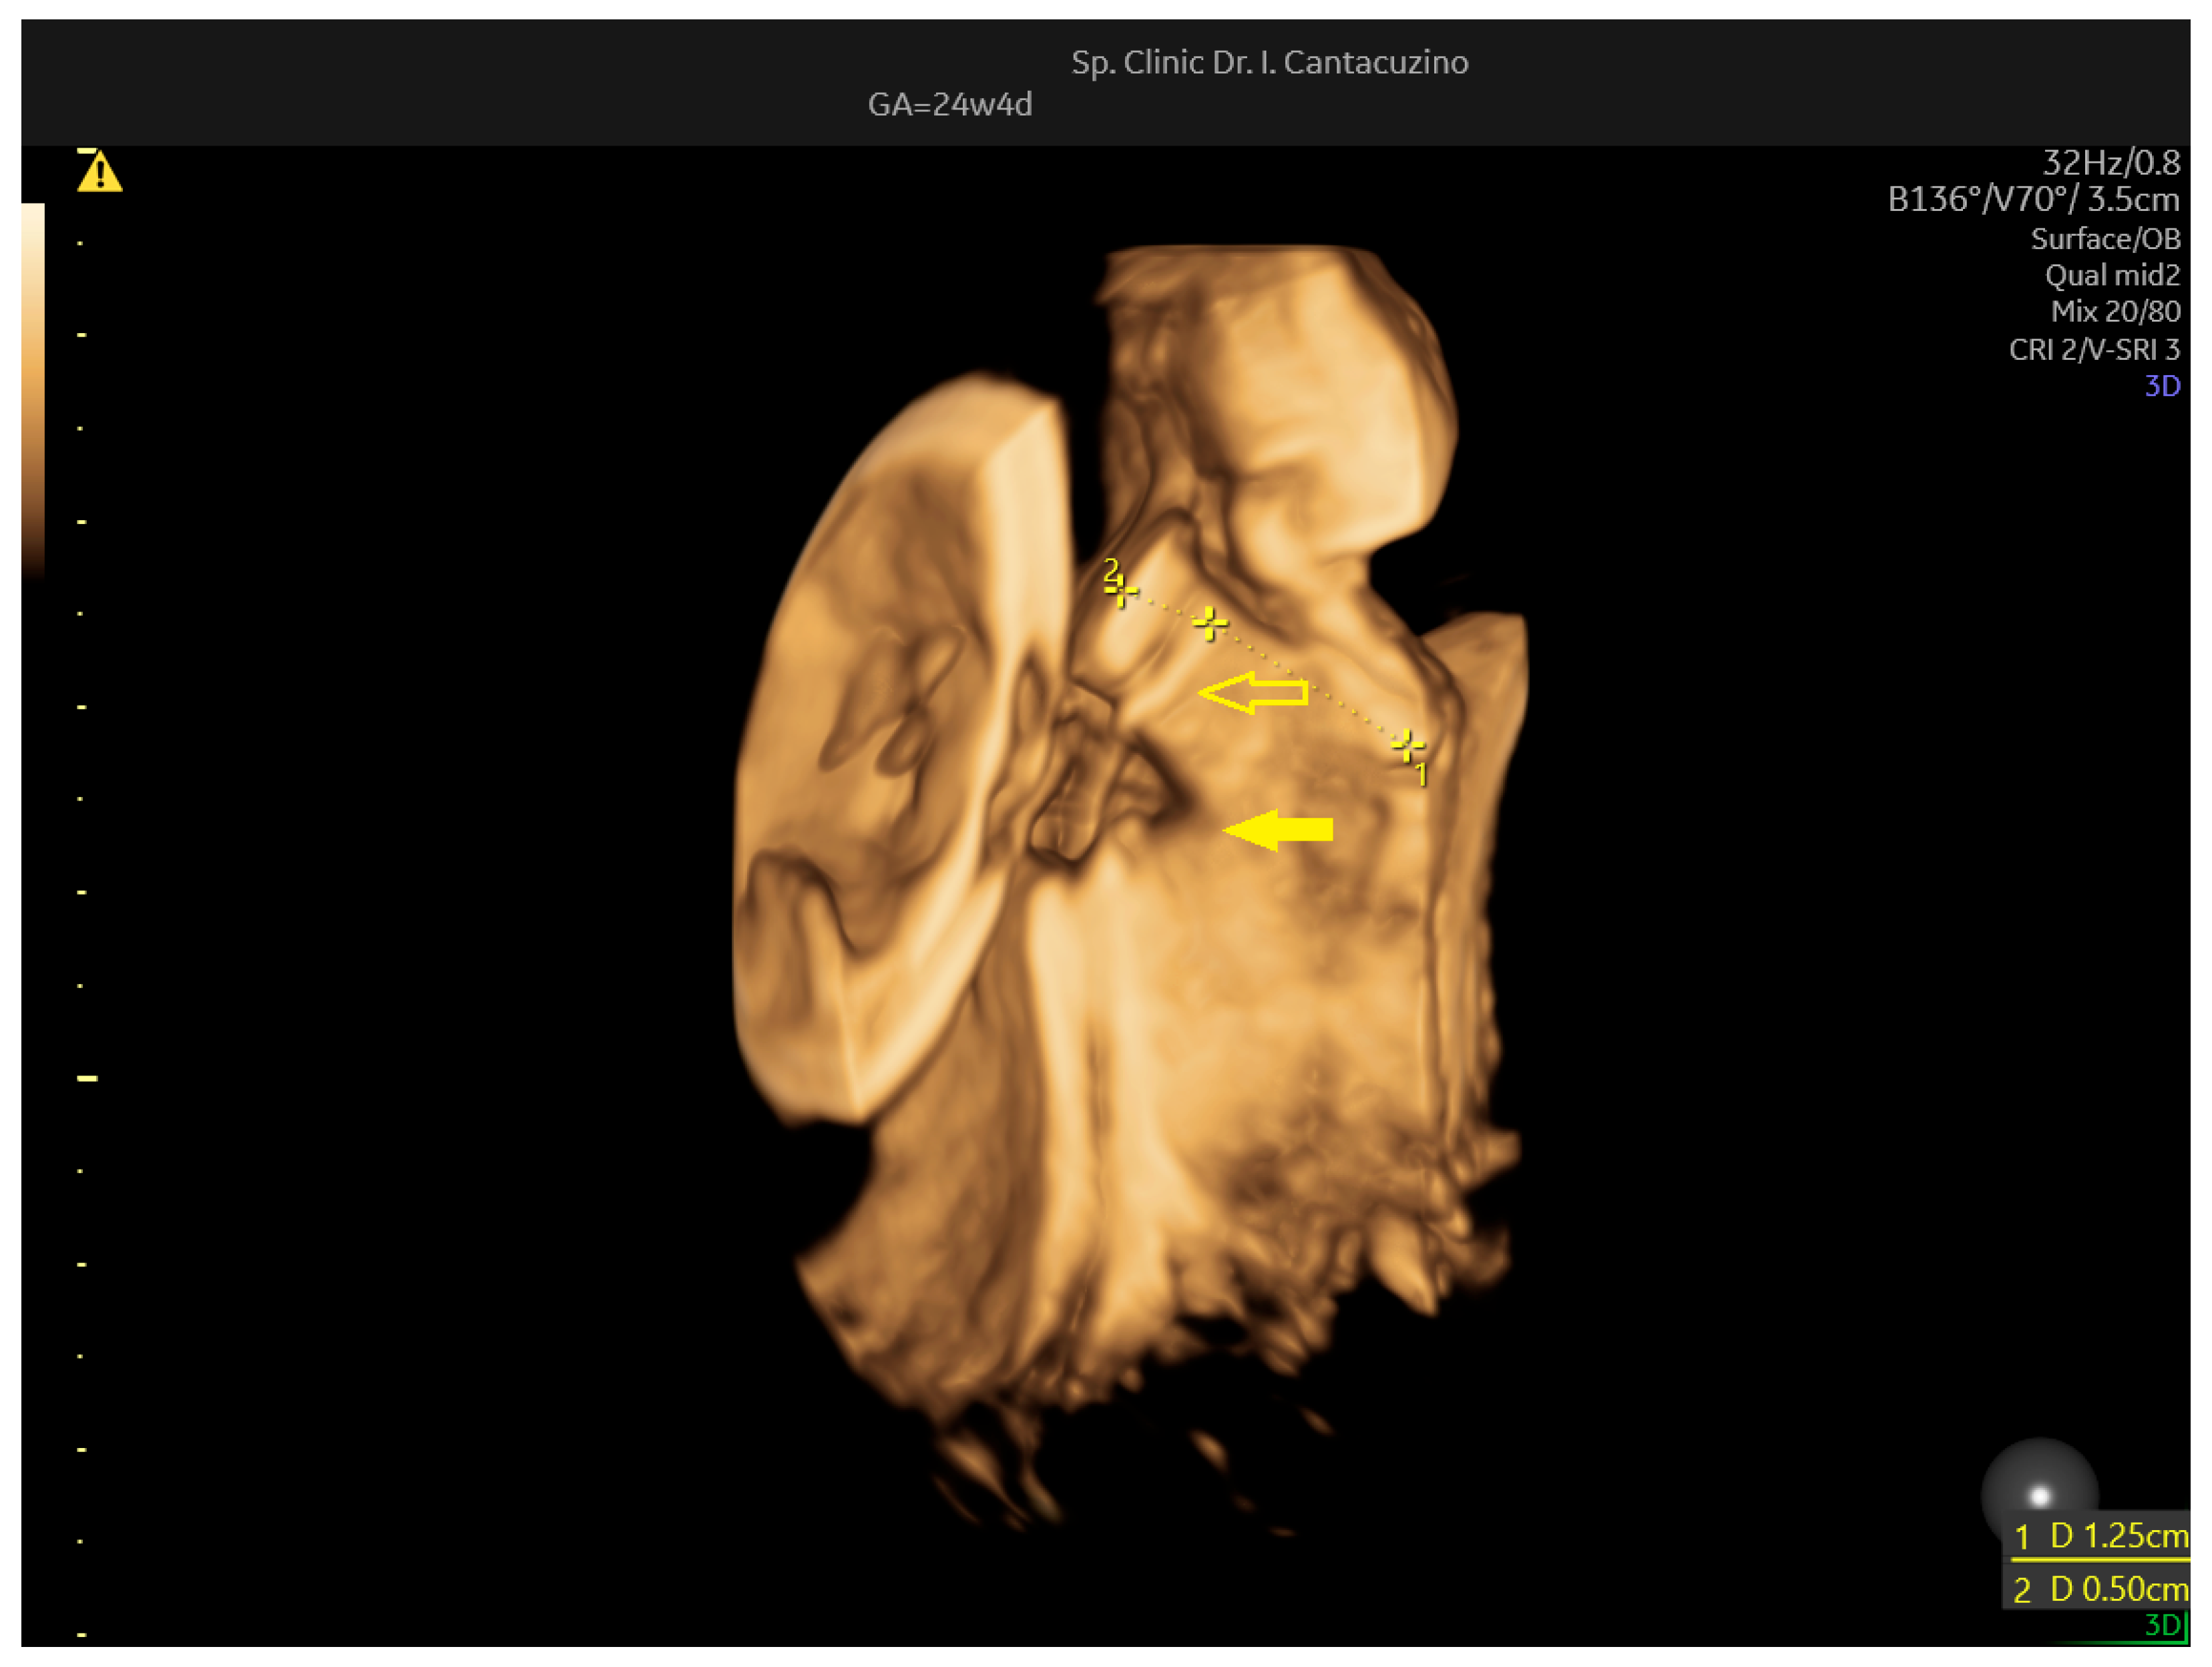

| Cervical length (mm) | 28 | 21.5 | 22.6 | |

| Cerclage thread—internal ostium distance (mm) | NA | 10.7 | 10.1 | |

| Cerclage thread—external ostium distance (mm) | NA | 10.8 | 12.5 | |